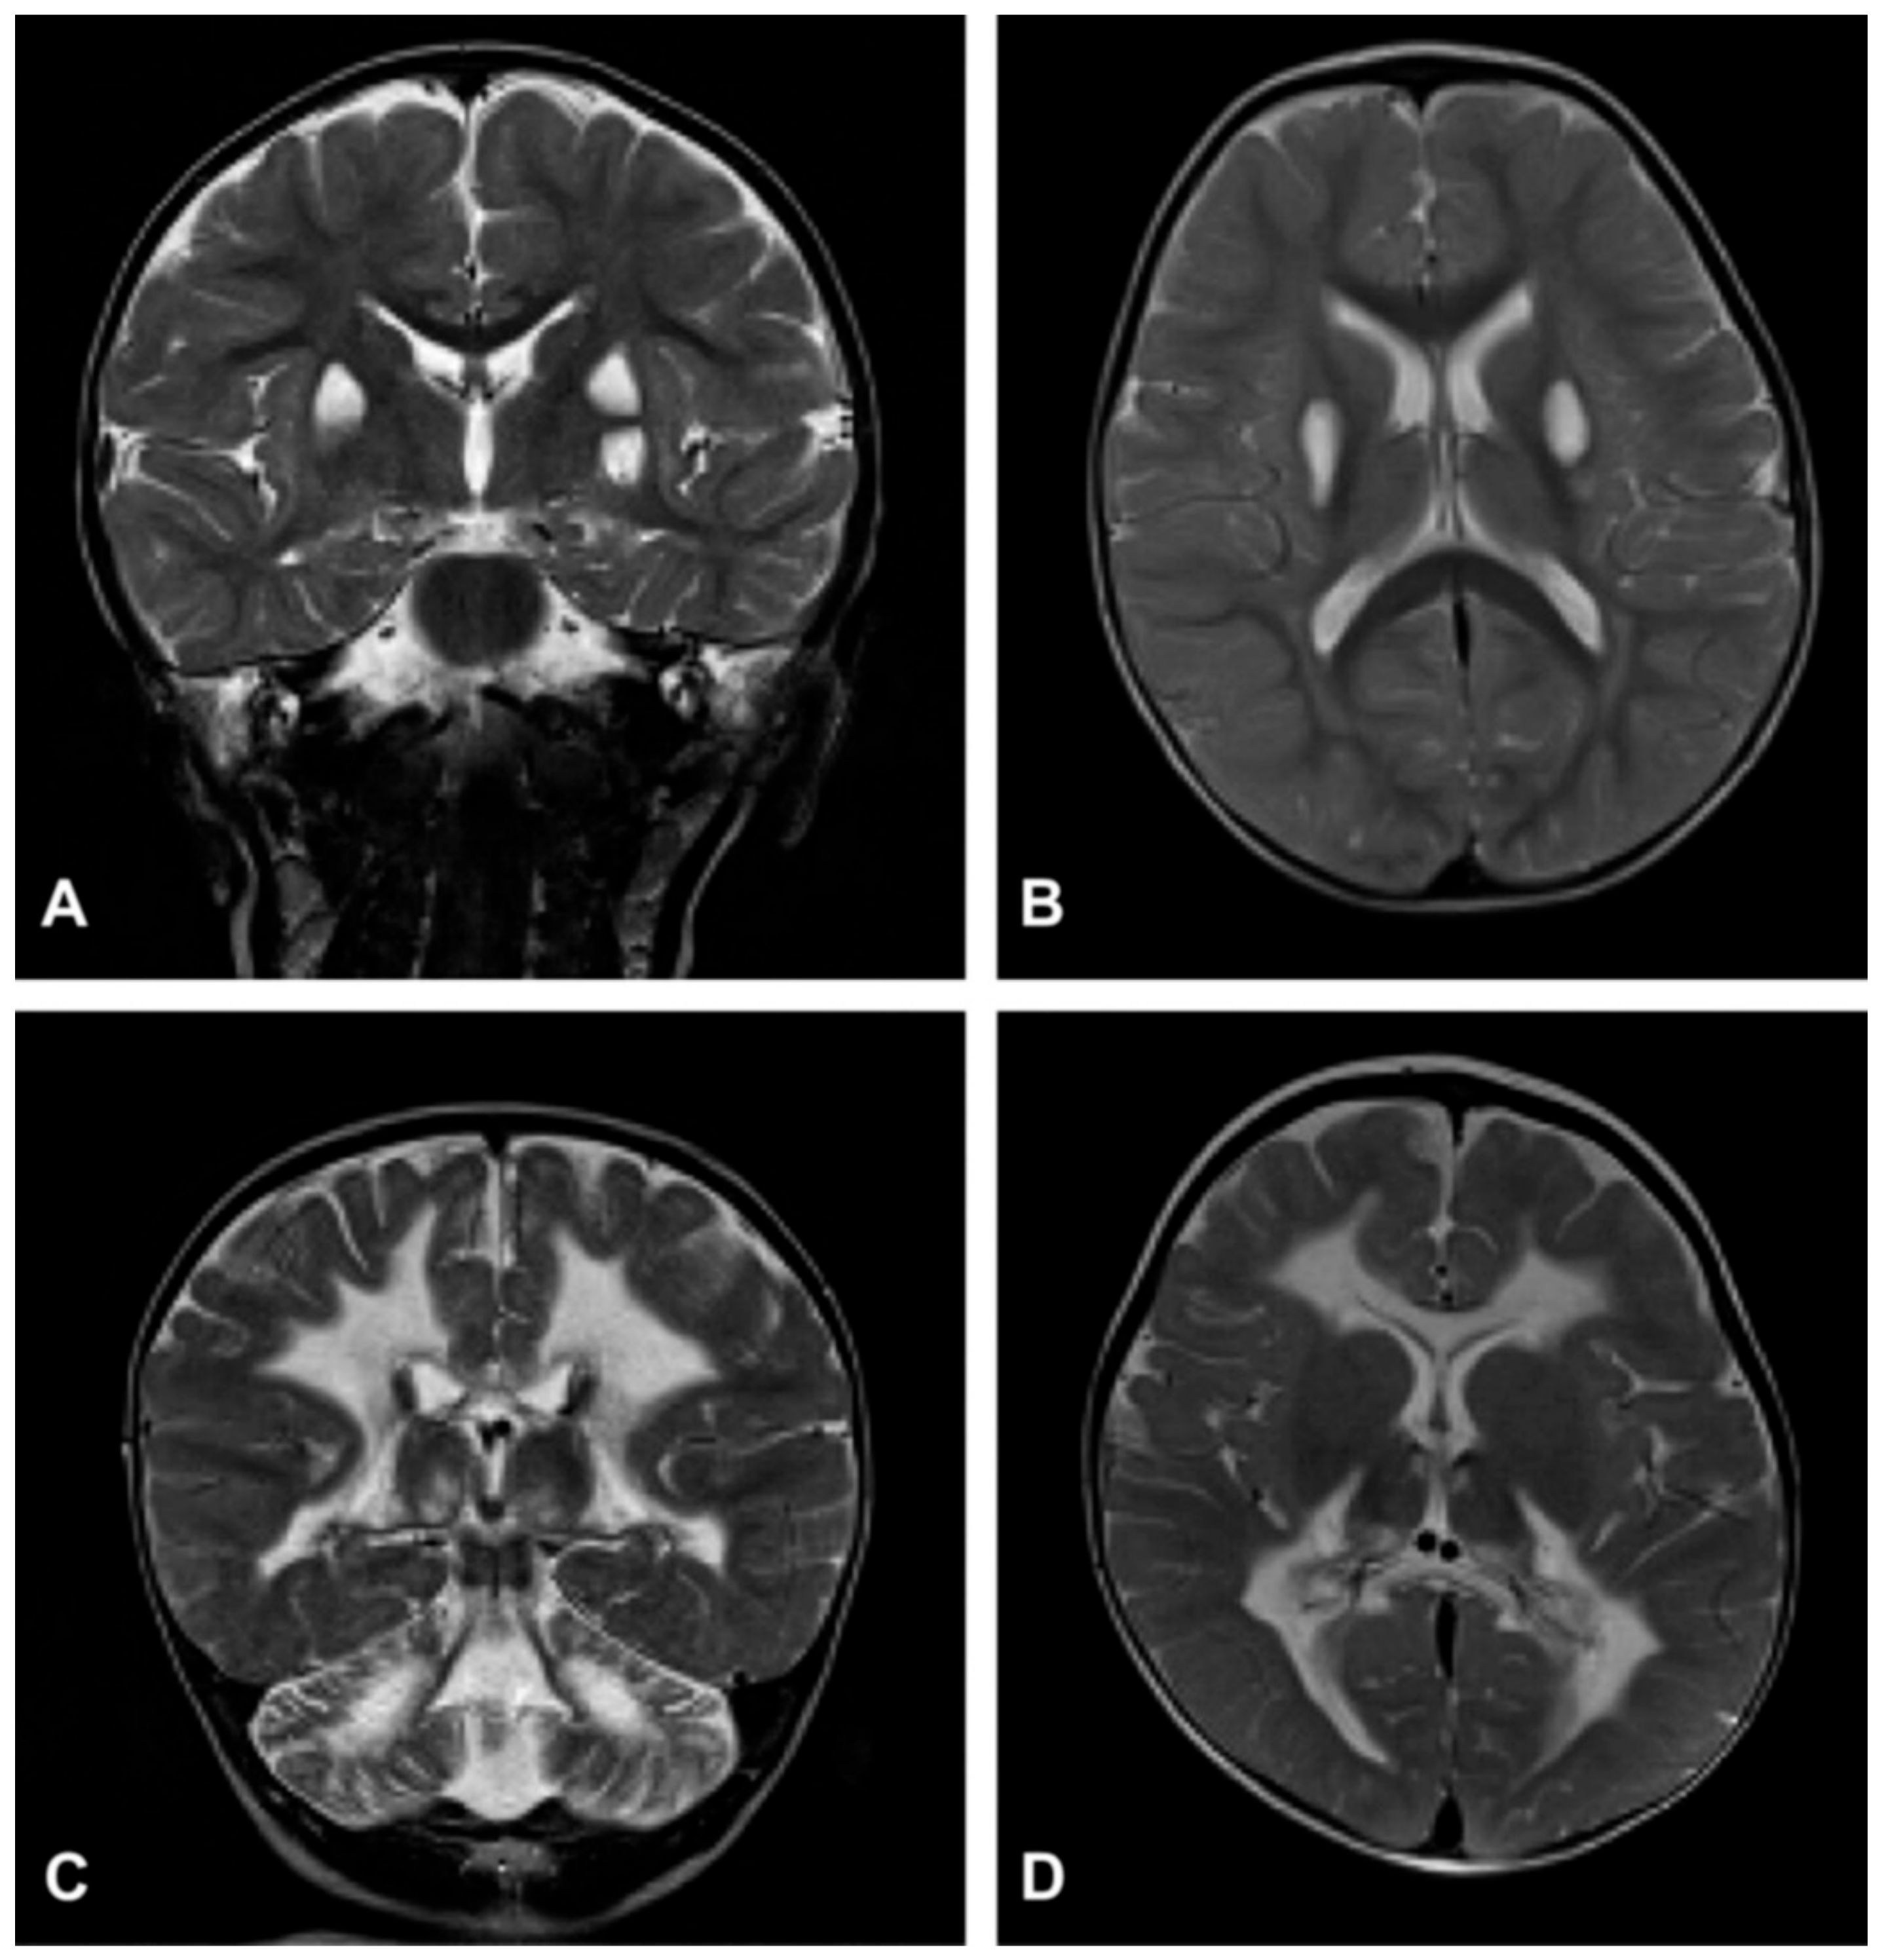

- Barkovich, A.J.; Good, W.V.; Koch, T.K.; Berg, B.O. Mitochondrial Disorders: Analysis of Their Clinical and Imaging Characteristics. AJNR Am. J. Neuroradiol. 1993, 14, 1119–1137. [Google Scholar] [PubMed]

- Oldfors, A.; Fyhr, I.M.; Holme, E.; Larsson, N.G.; Tulinius, M. Neuropathology in Kearns-Sayre Syndrome. Acta Neuropathol. 1990, 80, 541–546. [Google Scholar] [CrossRef]

- McKelvie, P.A.; Morley, J.B.; Byrne, E.; Marzuki, S. Mitochondrial Encephalomyopathies: A Correlation between Neuropathological Findings and Defects in Mitochondrial DNA. J. Neurol. Sci. 1991, 102, 51–60. [Google Scholar] [CrossRef]

- Tanji, K.; Vu, T.H.; Schon, E.A.; DiMauro, S.; Bonilla, E. Kearns-Sayre Syndrome: Unusual Pattern of Expression of Subunits of the Respiratory Chain in the Cerebellar System. Ann. Neurol. 1999, 45, 377–383. [Google Scholar] [CrossRef]